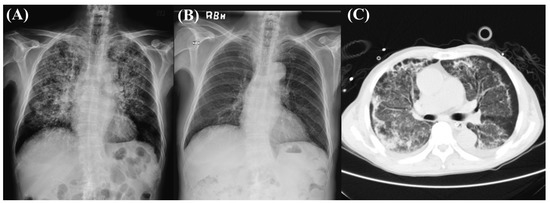

2. Case Presentation